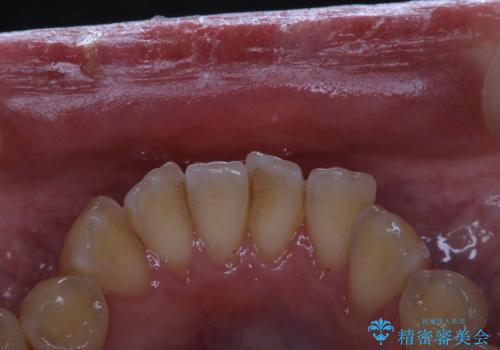

- しばらく、クリーニンングに来れなかったため、全体的な汚れが気になるとのことでした。PMTC60分コースを行いました。

毎日しっかりと歯磨きをしていても、日常生活での飲食物などにより着色してしまうことはあります。PMTCでは歯の表面の凸凹にミネラルを補給しツルツルの状態に仕上げます。定期的に行うことで歯質の強化になり着色が付きにくい状態になります。